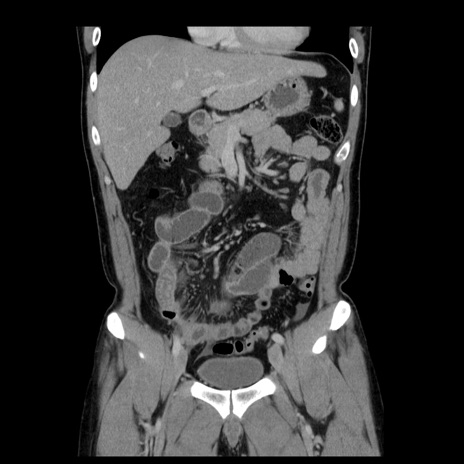

横断像

【症例】30歳代男性

【主訴】腹痛、嘔吐

【現病歴】昨晩から突然の腹痛あり、その後嘔吐、軟便も出現。腹痛が改善しないため救急搬送となる。2日前にしめ鯖の食事歴あり。

【身体所見】意識清明、苦悶様、BP 135/90mmHg、BT 35.7℃、腹部:平坦、やや硬、心窩部〜臍部に自発痛、圧痛あり、筋性防御+、反跳痛-

【データ】WBC 8100、CRP 0.57